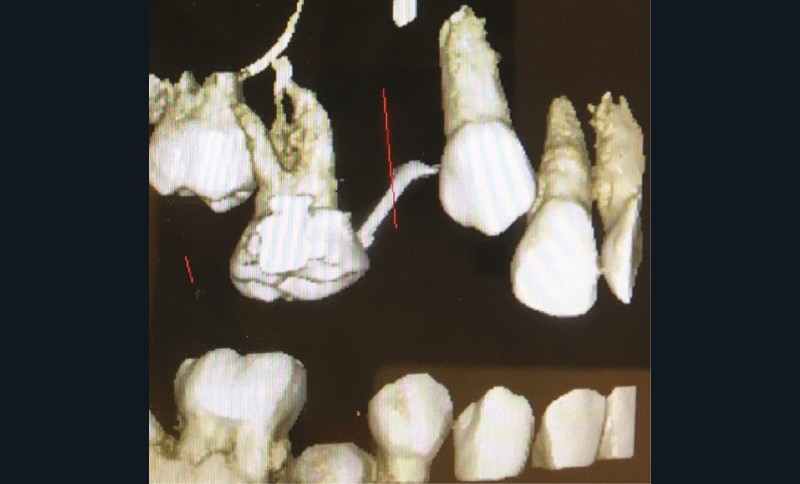

Un bilan radiologique 3D (Cone Beam CT) est prescrit dans le but d’évaluer, avec l’équipe de chirurgie du Dr Jean-Luc Charrier (Hôpital Bretonneau), la possibilité de transplantation d’une prémolaire du secteur 4 vers le secteur 1 et de définir le meilleur transplant possible entre 44 et 45. Sont analysées les dimensions du site receveur ainsi que l’anatomie, la position et l’état de maturation radiculaire des prémolaires candidates à la transplantation (fig. 3).

Cet examen nous apprend que :

- concernant le site receveur : son volume osseux est suffisant pour accueillir une des prémolaires du secteur 4 ;

- Concernant 45 :

- sa situation endo-osseuse (à l’abri de la flore bactérienne buccale et avec un desmodonte immature car non soumis aux stimuli occlusaux, facilitant une avulsion atraumatique) et son immaturité radiculaire franche (apex largement ouvert favorisant la revascularisation) font d’elle un transplant de choix ;

- mais il existe une proximité nette entre la couronne de 45 et la racine de 44, (augmentant le risque de lésion de 44 lors de l’avulsion de 45), et un rapport étroit entre la couronne de 45 et la corticale osseuse vestibulaire (augmentant le risque de lésion parodontale post-extractionnelle) ;

- enfin, 45 présente une longueur radiculaire encore courte risquant d’amener à un rapport couronne/racine limite in fine si l’édification radiculaire devait être stoppée après la transplantation de cette dent ;